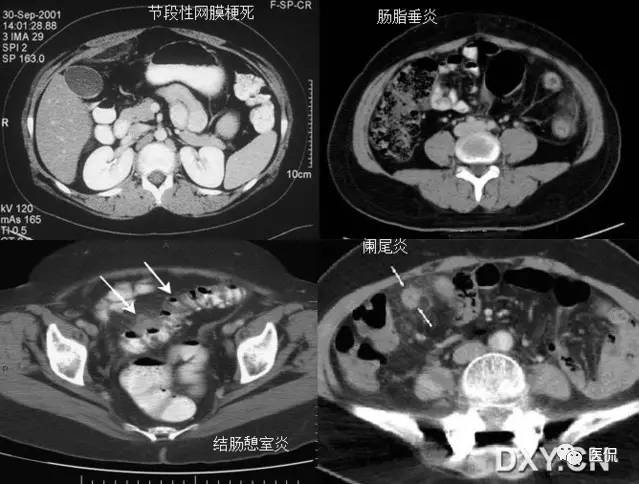

23 不成比例脂肪绞缠征

不成比例脂肪绞缠主要指的是增厚肠壁和周围脂肪在数量方面比例的严重失衡。在少数急性胃肠道疾病中,以肠壁相邻的肠系膜为中心而不是以肠壁为中心,因此肠壁周围脂肪增厚明显高于肠壁厚度。和这一征像相关的疾病主要包括4类:憩室炎、肠脂垂炎、网膜梗死和阑尾炎。胃肠道的大多数炎性疾病包括感染性的、非感染性的和局部缺血性的病变,都是以肠道为中心。这些疾病的肠壁增厚程度往往超过相邻脂肪条索的厚度。但是对于少数以肠壁临近系膜为中心的疾病,脂肪增生明显超过肠壁的厚度。

左上图:右侧腹横肌深面、胆囊内前方梭形囊性病变,有壁但不均匀,略有强化。与腹横肌成锐角,腹横肌肥厚。周围脂肪模糊,有索条点状影。

右上图:邻近降结肠远端系膜壁旁可见一卵圆形类似脂肪密度的病变,周边可见火焰样炎性改变,邻近肠壁有轻微增厚,无明显脓肿及肠梗阻征象。

左下图:肠壁增厚,结肠袋襞显影不良,以及结肠周围脂肪束条状改变。

右下图:CT显示壁明显增强的管状结构(箭头),右中腹的脂肪系膜反应。